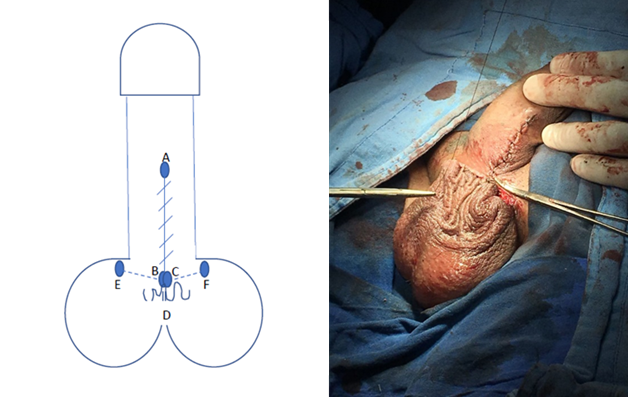

Se realiza protocolo prequirúrgico con documentación completa en el expediente clínico, ingreso del paciente para cirugía ambulatoria, con valoración anestésica, ayuno de 8 horas, baño previo al procedimiento, no se administró antibiótico profiláctico por no estar justificado, se realiza tricotomía según se necesite, se aplica asepsia antisepsia con iodopovidona. Se coloca lidocaína al 2% como anestésico local en el área quirúrgica en planos superficiales y profundos. La técnica quirúrgica aplicada en ambos casos se trata de una Plastia V-T, la cual consiste en realizar una incisión sobre la cuerda en forma de v invertida para despegar las capas de la piel de su adherencia aberrante en la cara ventral del pene (Figura 1 y 2), se afronta la nueva base del pene con sutura absorbible (Figura 3 y 4) , posteriormente se realiza incisiones laterales a la base del pene y coincidiendo a la raíz de la piel del escroto para distribuir toda la piel escrotal sobrante de manera uniforme, esto confiere la forma final de una T invertida (Figura 5 y 6).

Figura 4 Se sutura B con C para formar la nueva base del pene en su cara ventral y afrontando el resto de la piel del trayecto A con B-C, quedando la piel redundante, D, debajo.

Figura 5 Se trazan los puntos E y F lateralmente de la base del pene para ampliar la superficie de afrontamiento de la piel escrotal redundante y se sutura el escroto (D) a estas alas laterales (E y F)

Podemos observar que posterior a la realización de la circuncisión, se realizó paso a paso la técnica propuesta como podemos observar en las Figuras 1-6 que corresponden al caso 1 que fue el más representativo de la técnica.

En la técnica propuesta se logra respetar el sentido del rafe peneoescrotal, y el la incisión horizontal permite distribuir la ganancia de la piel escrotal de una manera uniforme para que cuando el pene este en erección, la dinámica de tensión en la piel tenga piel redundante en la base y evite la formación de pliegues a la tracción, además, en las imágenes se aprecia como se logra la separación total del pene del escroto, lo cual es uno de los principios básicos de la técnica quirúrgica (Figura 2), lo cual se logra como en ninguna otra descrita.